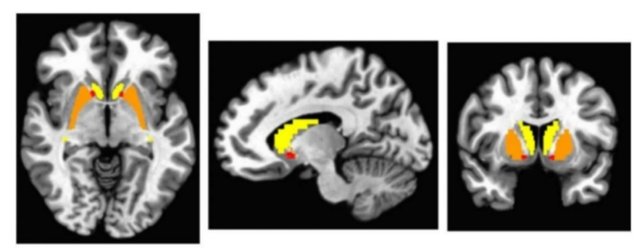

صور للدماغ تظهر مناطق الفحص المتعلقة بإشارات الدوبامين في حالات التوحد.

انطلاقاً من هذه الخلفية، اتبع فريق بحثي من جامعة ميسوري الأمريكية منهجاً جديداً. استخدم الباحثون تقنية فحص متخصصة للدماغ تُسمى “دايت سبيكت” (DaT SPECT)، والتي تُستخدم عادة لتشخيص الباركنسون لدى كبار السن. هذا الاستخدام لتقنية مخصصة للمسنين على الشباب يشكل نقطة تحول.

يقول ديفيد بيفيرسدورف، طبيب الأعصاب والباحث الرئيسي من جامعة ميسوري: “أبحاث سابقة ركزت على إجمالي كمية الدوبامين في أدمغة المصابين بالتوحد. لكننا اتخذنا مساراً مختلفاً، بحثنا عن أي خلل في طريقة معالجة الدوبامين في جزء محدد من الدماغ يُدعى ‘العقد القاعدية’ عبر نواقل الدوبامين”. هذا التغيير في زاوية البحث قد يفتح آفاقاً جديدة، أو يعقد الصورة أكثر.

فحص الباحثون أدمغة اثني عشر شاباً مصاباً بالتوحد، تتراوح أعمارهم بين 18 و24 عاماً. كشفت الفحوصات عن سلوك غير طبيعي لنواقل الدوبامين لدى اثنين منهم، مع وجود “احتمال لخلل” لدى اثنين آخرين. لم تظهر النواقل أي تشوهات أو عدم تماثل منتظم كما كان متوقعاً، وهي نتيجة تحتاج إلى تفسير دقيق.